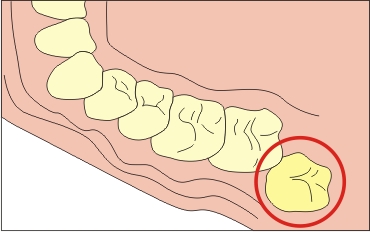

Disztópikus nyolc (kívül található fogsorív)

Kívül található fogsorív bölcsességfog is kombinálható egy lejtőn bármely irányba.